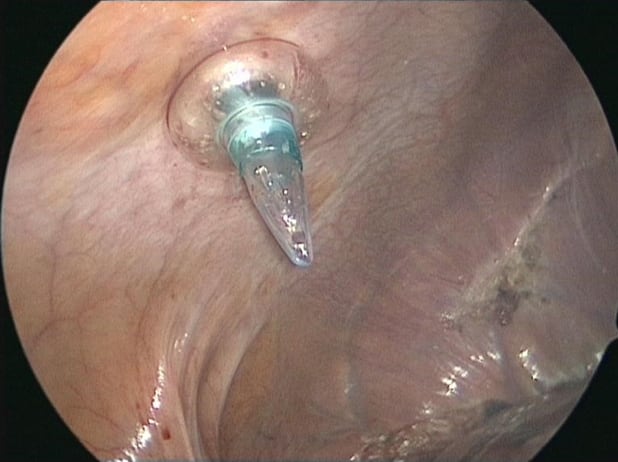

Intercostal port for anatomical segment 7 resection